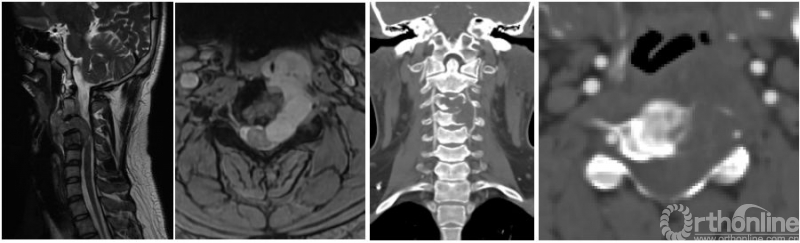

图1,颈椎MRI和CT

病人的核磁和CT显示了一个以C3-4椎间孔为中心的哑铃型肿瘤,并且伴有C3和C4椎体的骨质破坏(图1)。这些片子给我的第一印象也是神经源性肿瘤。伴有椎体破坏的神经鞘瘤并不少见,比如下面这个病例就是一个经过手术证实的累及椎体的哑铃形神经鞘瘤(图2)。